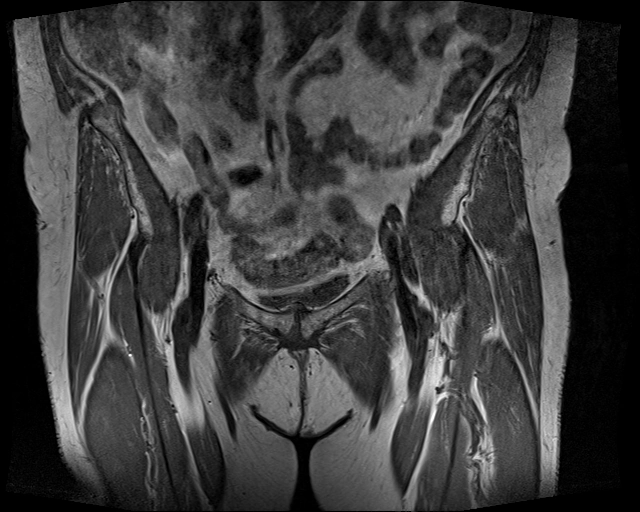

Hoại tử vô mạch chỏm xương đùi (Osteonecrosis of the femoral head)